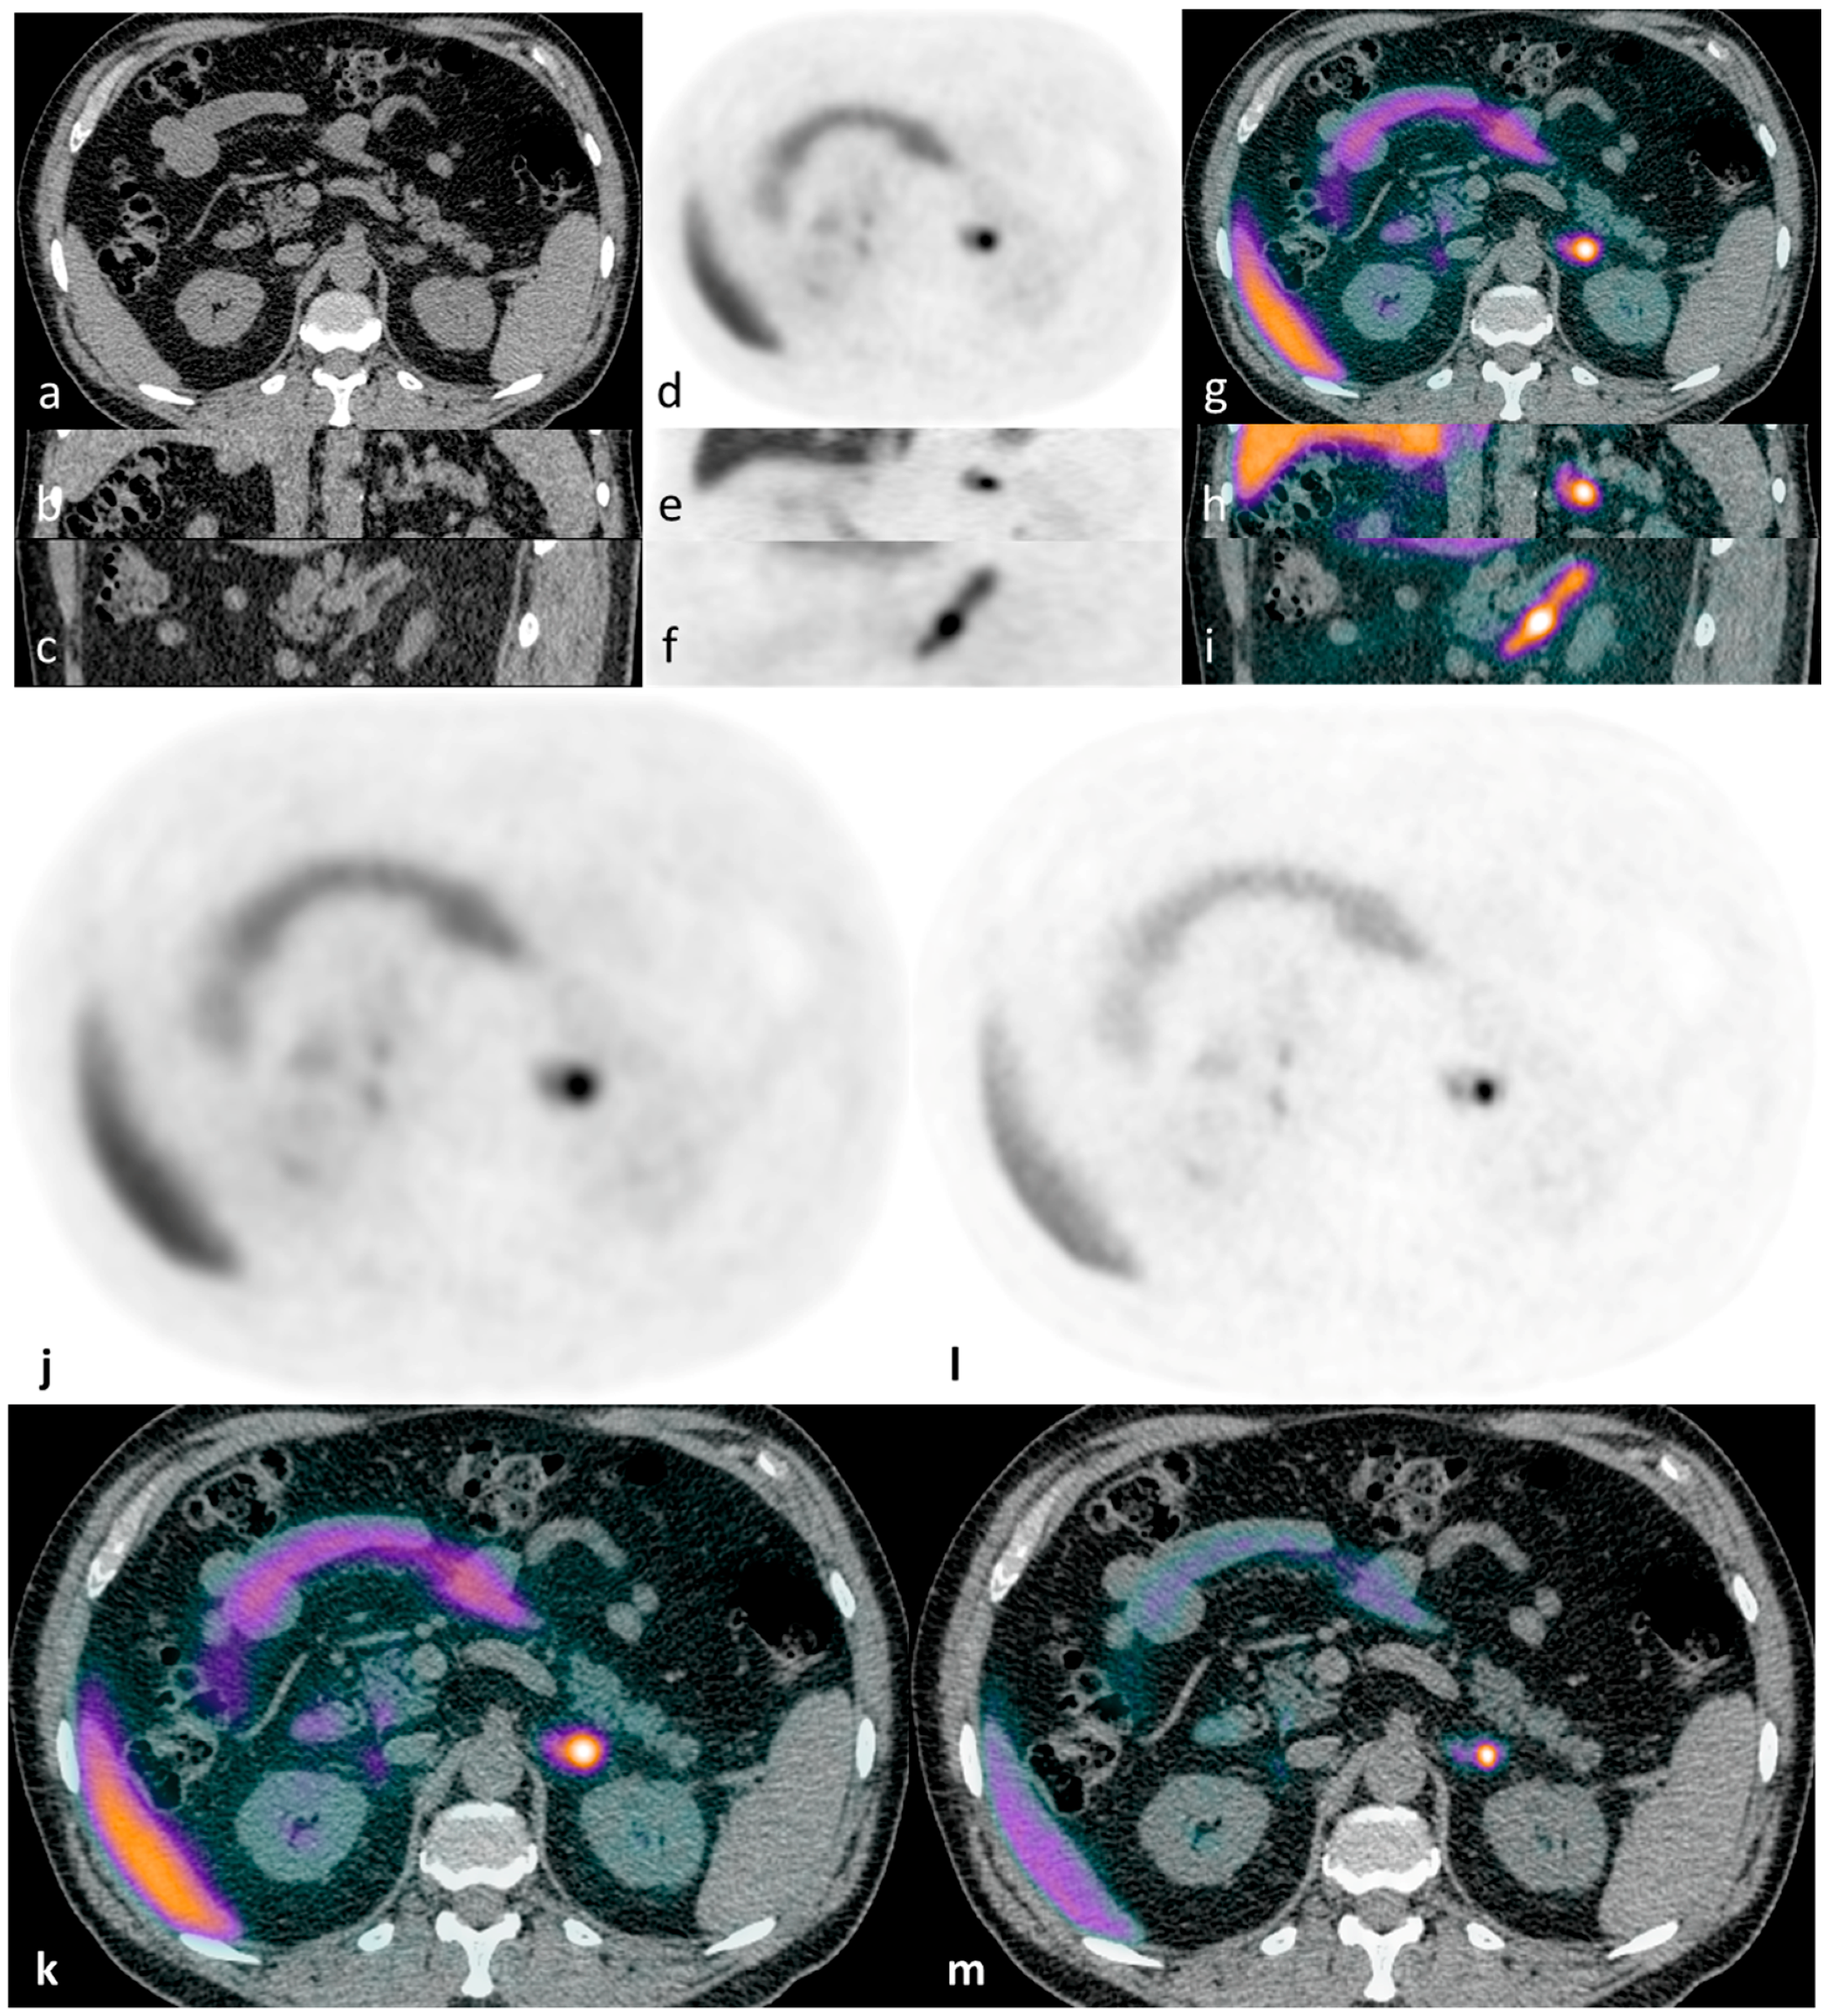

Figure 4. Illustrative case 4: A 40-year-old man with a five-year history of hypertension and hypokalaemia had a diagnosis of hyperaldosteronism confirmed by failure to suppress aldosterone following saline infusion. CT findings were equivocal, showing a possible small right adrenal nodule (a). Tracer uptake was symmetrical bilaterally on 11C-metomidate PET-CT (b,c). His bilateral disease is managed medically.